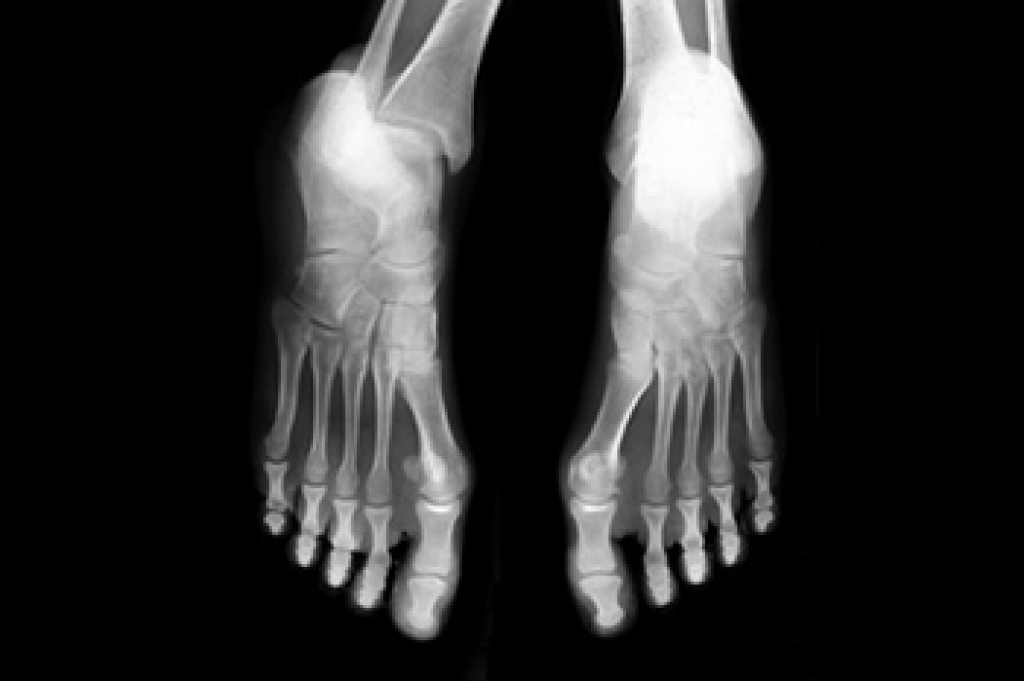

Flatfoot is a condition in which the arch of the foot is depressed and the sole of the foot is almost completely in contact with the ground. About 20-30% of the population generally has flat feet because their arches never formed during growth.

- Flat look to one or both feet